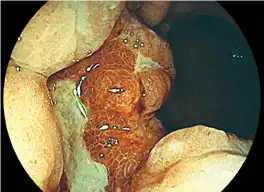

CMOS Technology produces advanced FICE image

Through higher resolution and improved noise reduction, FICE images are more sharp and clear than ever.

It enables easier differentiation between lesion-affected and non-affected tissue.

FICE 1 Stomach